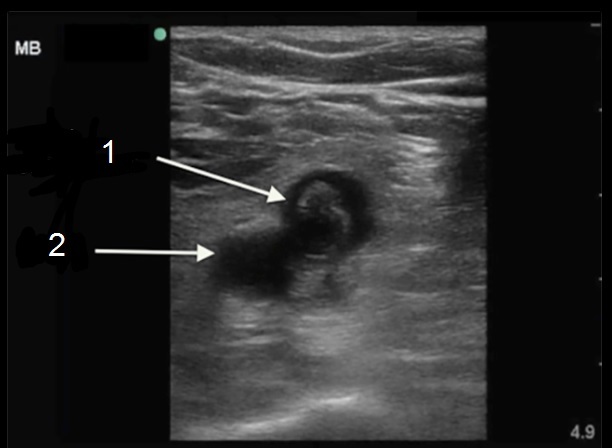

Imagen 1 de trombosis venosa profunda (TVP), trombo en la vena poplítea

1. Trombosis venosa profunda (TVP) crónica de la vena poplítea

2. Arteria poplítea